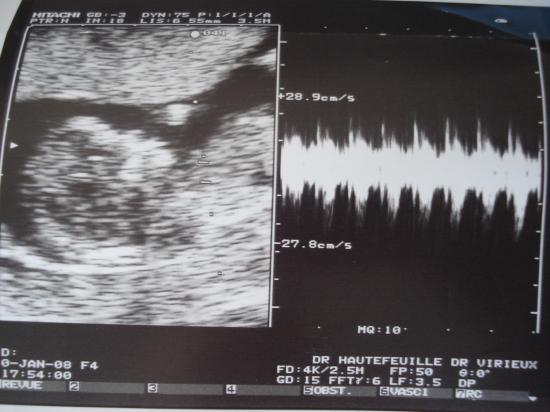

A 12 semaines et 2 jours, Bébé mesurait déjà 55mm, on aperçoit sur cette échographie, sa tête, son corps et ses jambes, c'est un moment tellement emouvant cette première rencontre !

Nous arrivons même à ententre les battements de son coeur